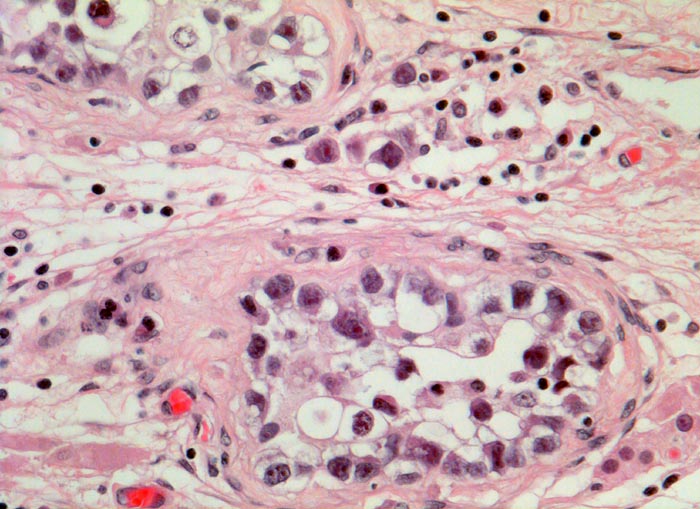

PathoPic – image database / PathoPic ID 3082 - Seminom und testikuläre intraepitheliale Neoplasie (TIN)

Seminom und testikuläre intraepitheliale Neoplasie (TIN)

Im Interstitium lassen sich lediglich vereinzelte Seminomzellen nachweisen. Die invasiven Zellen gleichen den intratubulären atyischen Keimzellen.

Intratubuläre atypische Keimzellen finden sich nahezu bei jedem malignen Keimzelltumor des Hodens. Wenn die atypischen Zellen im tumorfreien Hoden nachweisbar sind, wird dieser in der Regel bestrahlt. Die atypischen Keimzellen enthalten viel Glykogen und sind daher PAS positiv. Ausserdem sind sie positiv für die plazentäre alkalische Phosphatase PLAP. Meist wachsen die Seminome als grössere Knoten infiltrierend. Daneben kann man auch wie im vorliegenden Fall mikroskopisch kleine Gruppen von Seminomzellen im Interstitium finden, welche über den ganzen Hoden verteilt sein können.